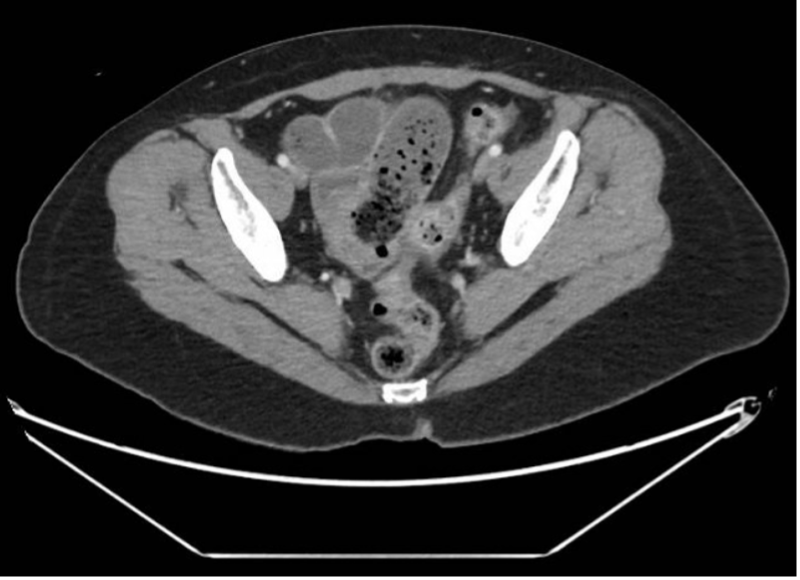

Small bowel obstruction with transition point in the pelvis at the level of wall-thickened distal ileum.

Diffuse wall thickening of the terminal ileum